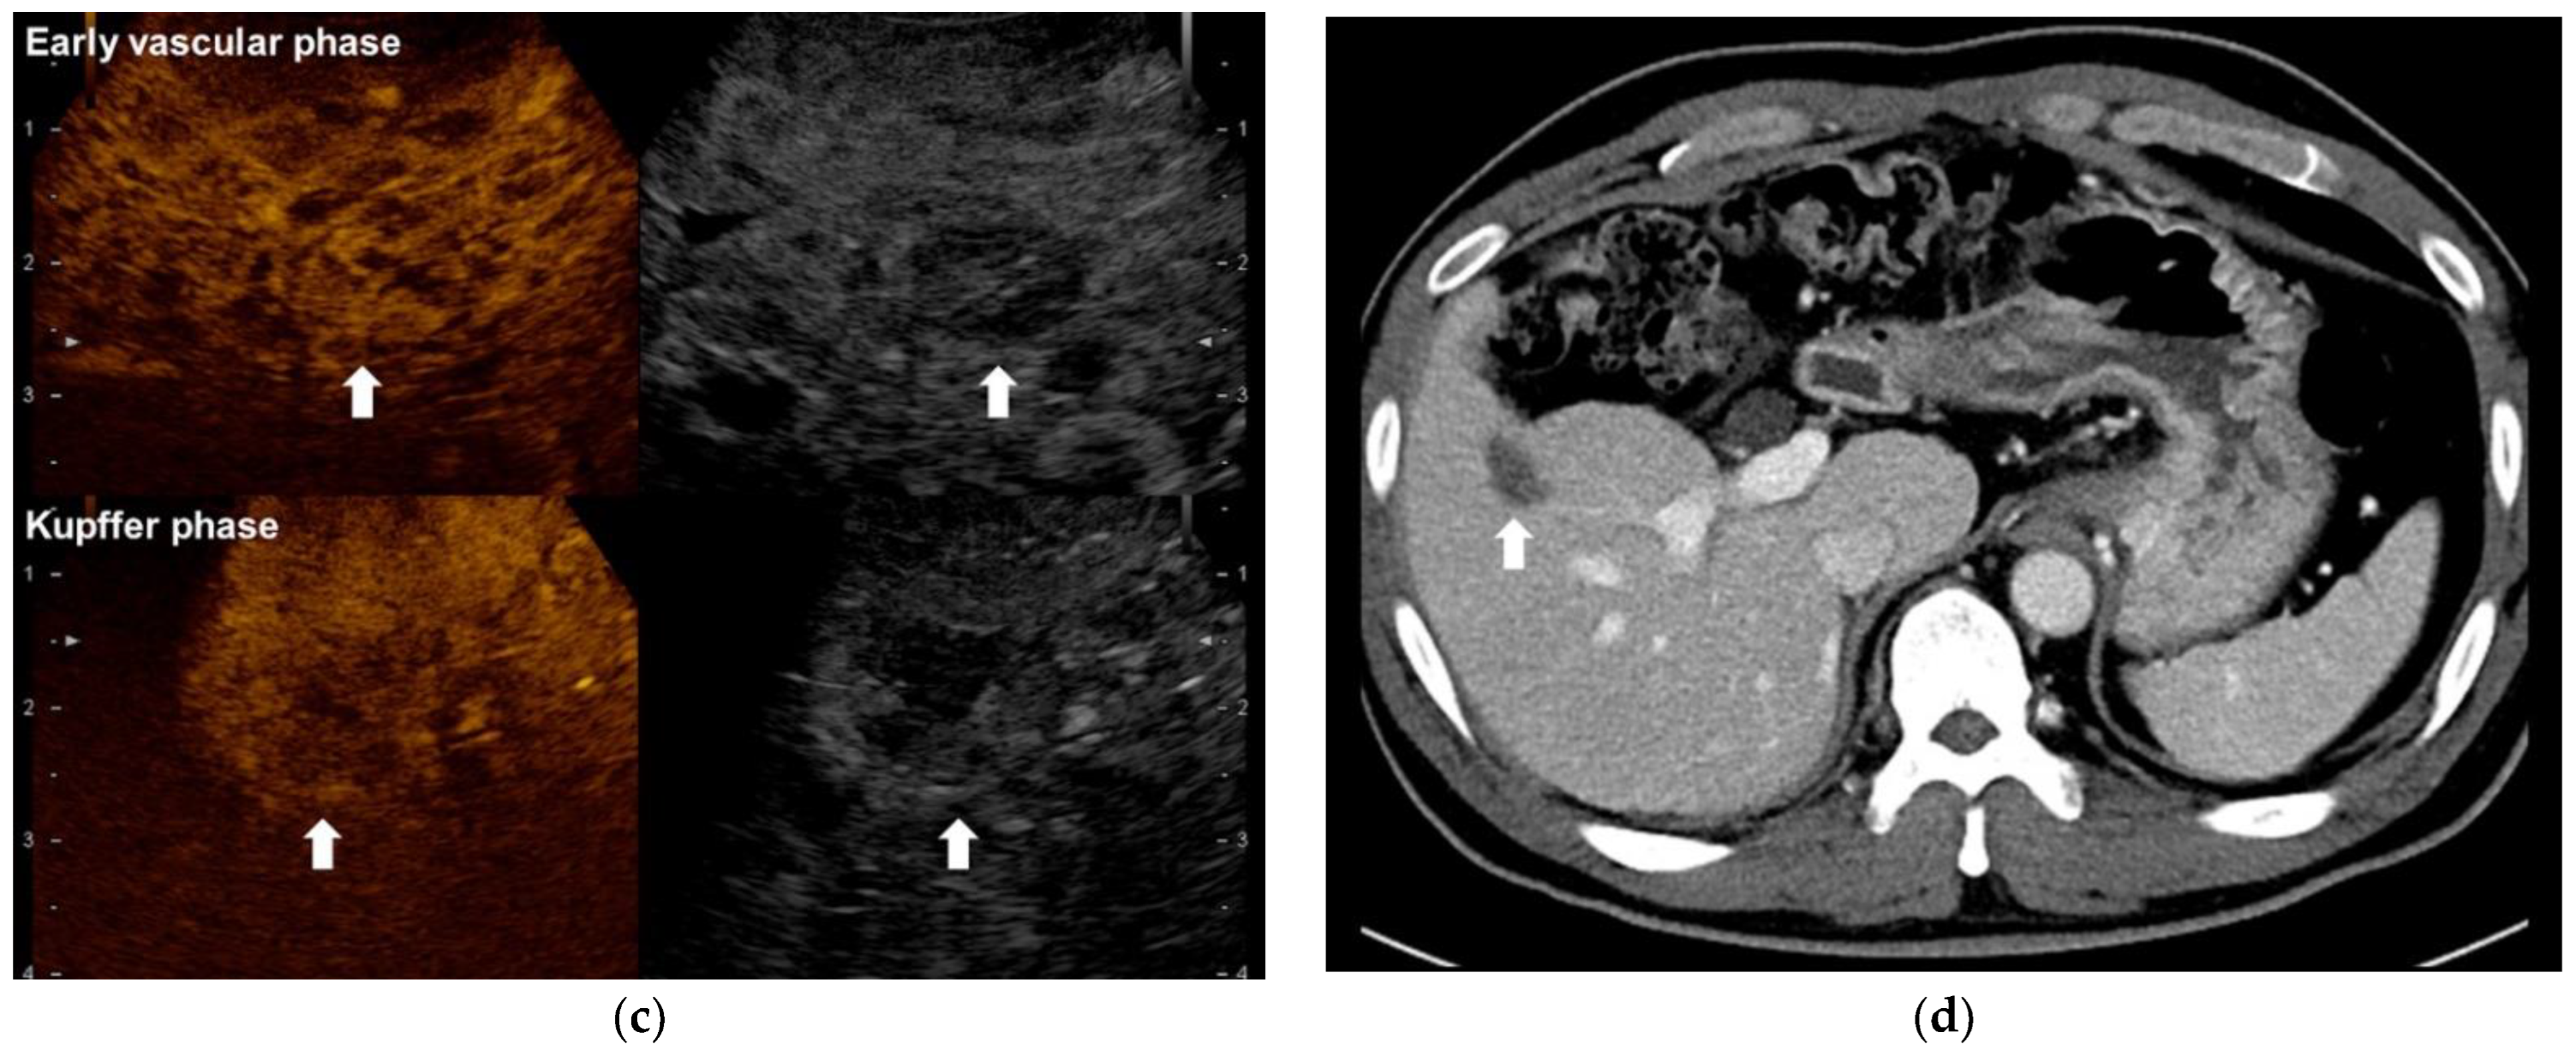

2.2. Surgical Resection plus Intraoperative Radiofrequency Ablation

- Park, H.S.; Kim, Y.J.; Yu, M.H.; Jung, S.I.; Jeon, H.J. Real-time contrast-enhanced sonographically guided biopsy or radiofrequency ablation of focal liver lesions using perflurobutane microbubbles (sonazoid): Value of Kupffer-phase imaging. J. Ultrasound Med. 2015, 34, 411–421. [Google Scholar] [CrossRef] [PubMed] [Green Version]